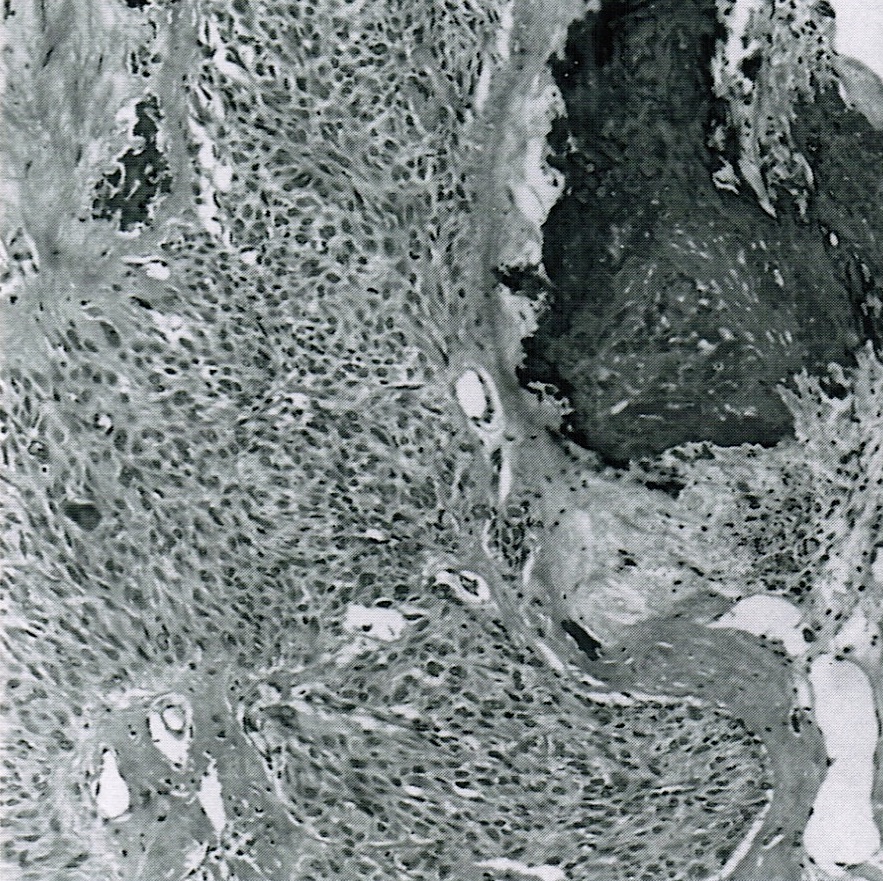

Microscopic (histologic) description

- Predominant population of cells showing ovoid to round nuclei and pale gray cytoplasm, which can be abundant

- Minor component of the tumor may have spindled nuclei, reflecting overlap between fibroma and thecoma

- Indistinct cell membranes impart a syncytial appearance

- Diffuse or nodular growth pattern

- Absent or minimal nuclear atypia

- Mitotic rate usually < 5/10 high power fields

- Hyaline plaques

- Cytoplasmic lipid vacuoles may be present but are not essential

- May show aggregates of cells with brightly eosinophilic cytoplasm (lutein cells)

- Calcification is more common in young patients (Int J Gynecol Pathol 1988;7:343)

- Uncommon features include keloid-like sclerosis, nuclear grooves, bizarre nuclear atypia (Am J Surg Pathol 2014;38:1023)

- Rarely contains a minor component of sex cord elements (Int J Gynecol Pathol 1983;2:227)

- Malignant thecoma: very rare, diagnosis requires diffuse moderate to severe nuclear atypia and high mitotic rate (> 4/10 high power fields) (Am J Surg Pathol 2011;35:e15)

Microscopic (histologic) images

Contributed by Victoria Collins, M.D., Tamara Kalir, M.D., Ph.D., AFIP and @SeoparjooAzmel on Twitter